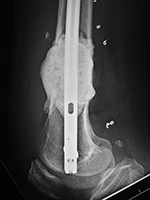

AP and lateral views of the knee show a distal femoral cadevaric limb sparing allograft approximated to the native distal femoral stump by a retrograde intramedullary nail. Two interlocking cannulated screws go through the distal portion of the nail. Cruciate ligament and capsular reattachment were performed with two interference screws and two staples in the proximal tibia and a staple in the posterior aspect of the allograft metaphysis. The patient had a non-specified distal femur sarcoma.